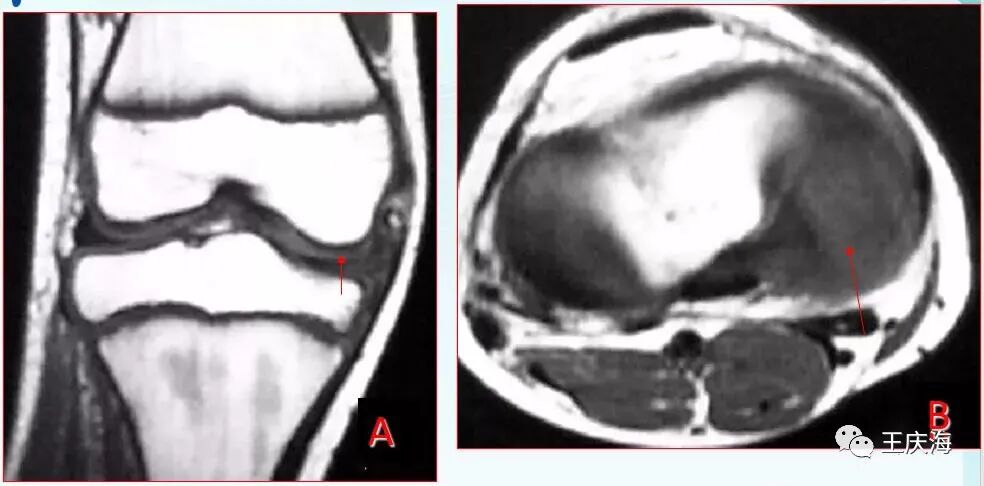

小盘状半月板

冠状面(图A)见外侧半月板体部宽度增宽,横断面(图B)示外侧半月板环较小。